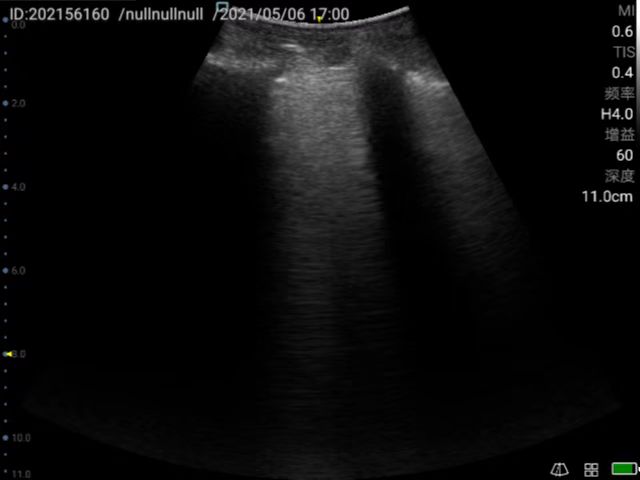

Musculoskeletal ultrasound technology (referred to as musculoskeletal ultrasound) has developed rapidly domestically, and has been continuously promoted and applied in clinical practice. It has become the first choice or gold standard in the diagnosis and treatment of many diseases, such as peripheral nerve diseases, muscle and tendon acute and chronic diseases, early diagnosis and differential diagnosis of rheumatism and rheumatoid diseases. Rehabilitation medicine has developed rapidly in recent years. With the aging of the population, the development of the hierarchical diagnosis and treatment system, and the emergence of precision medicine, medical imaging, especially ultrasound medicine, plays a very important role in rehabilitation medicine. At present, rehabilitation medicine in our country relies on traditional physical examinations, and its blindness, randomness, untargetedness and lack of objective indicators for judging efficacy have attracted more and more attention. Musculoskeletal ultrasound has the advantages of non-invasiveness, convenience and practicality which can be used as the first-choice imaging examination for rehabilitation medicine. Ultrasound positioning and ultrasound-guided puncture injection technology have become the "third eye" of rehabilitation physicians which has an irreplaceable role in manipulative therapy, rehabilitation equipment therapy, injection therapy and sports rehabilitation, etc.

Peri-articular injection to help diagnose and guide injection of anti-inflammatory drugs for frozen shoulder.

Application in joint ultrasound (wrist, shoulder, elbow, hip, knee, ankle, etc.); Therapeutic application of muscle, tendon, myofascial pain syndrome; Application in urinary system rehabilitation; Application of ultrasound-guided botulinum toxin injection therapy; Applications of Neurosonography; Applications of Cardiac Ultrasound; Application of interventional ultrasound (interventional treatment of joint disease, cystic disease); Expanded application of ultrasound in traditional medicine (ultrasound visualization acupotomy technology); Application of pelvic floor ultrasound in rehabilitation of diseases; Application of ultrasound-guided puncture in pain.